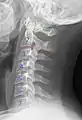

Cervical lines are annotations used in medical imaging of the cervical vertebrae, here seen on X-ray and CT, respectively. Incongruencies indicate cervical fracture, spondylolisthesis and/or ligament injury.